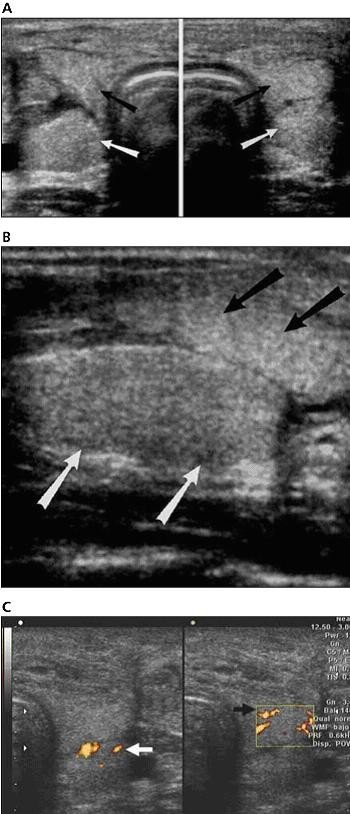

six months after the transplantation, a neck ultrasonographic scan was performed with a high-resolution linear transducer (voluson 730 pro; ge healthcare, waukesha, wi) that showed the transplanted thyroid gland anterior and caudal to the native thyroid (figure 1, a and b). both glands were normal in echogenicity and size. gray scale real-time ultrasonography showed a normal appearance of the inferior transplanted thyroid arteries. color doppler ultrasonography proved vascular perfusion and allowed visualization of the right superior thyroid artery. power doppler ultrasonography showed normal flow within the transplanted thyroid gland (figure 1c). b-mode ultrasonography showed normal dilatation of the carotid artery at the site of the arterial anastomosis (figure 2a); color doppler ultrasonography showed reversal of flow at that point (figure 2b). spectral doppler ultrasonography was performed at the origin of transplanted thyroid arteries and showed peak systolic speeds between 32 and 48 cm/s and end-diastolic velocities between 9 and 13 cm/s with high-resistance waveforms (figure 3b). the evaluation of venous anastomoses was not possible because there were no changes in internal jugular veins allowing differentiation from native thyroid veins. spectral analysis showed both arterial and venous flow within the transplanted thyroid gland, the latter being an indirect sign of patency of the venous anastomoses.

移植手术中将供者气管近端与第一个气管环吻合,将远端在隆凸水平上3cm处吻合。根据手术医生从先前的动物试验模型中发展来的技术,将气管连带甲状腺进行了移植。同时将供者甲状腺下动脉和受者的颈总动脉吻合,将右甲状腺上动脉和受者同侧颈外动脉吻合,甲状腺中静脉与颈内静脉吻合,甲状腺下静脉与无名静脉吻合。2个月后,dsa显示血管(动脉)灌注良好,检查期间静脉相显示不清。病人术后进展平稳,除了有过一次的乳糜胸但也解决了。术后病人拔除了插管,也没出现呼吸困难,予以免疫抑制剂治疗防止排异反应。移植手术后6个月,应用高分辨率的探头行颈部超声检查(ge voluson730 pro),显示移植的甲状腺位于前面,自身甲状腺在后(图1,a和b),两腺体的回声和大小正常。灰阶实时超声扫描显示移植甲状腺下动脉形状正常。彩色多普勒超声证实血管充盈良好,右侧甲状腺上动脉充盈良好。能量多普勒显示移植甲状腺内血流正常(图1,c)。b型超声显示动脉吻合处颈动脉正常扩张(图2,a)。彩色多普勒显示此处血流反转(图2,b)。频谱多普勒超声显示移植甲状腺动脉起始点的收缩期峰值流速在32-48cm/s,舒张末期流速在9-13cm/s,呈高阻力波形(图3,b)。由于无法区分自身甲状腺静脉和颈内静脉,因此静脉吻合处的检查不能评估。频谱多普勒显示移植甲状腺内的动脉和静脉分布正常。后者间接表明了静脉吻合处是开放的。

图2 a,b超纵切面显示18岁的患者气管移植后的动脉吻合处的颈动脉正常扩张。b,彩色多普勒纵切面图像:蓝色区(箭头)显示动脉修补处的血管反转。